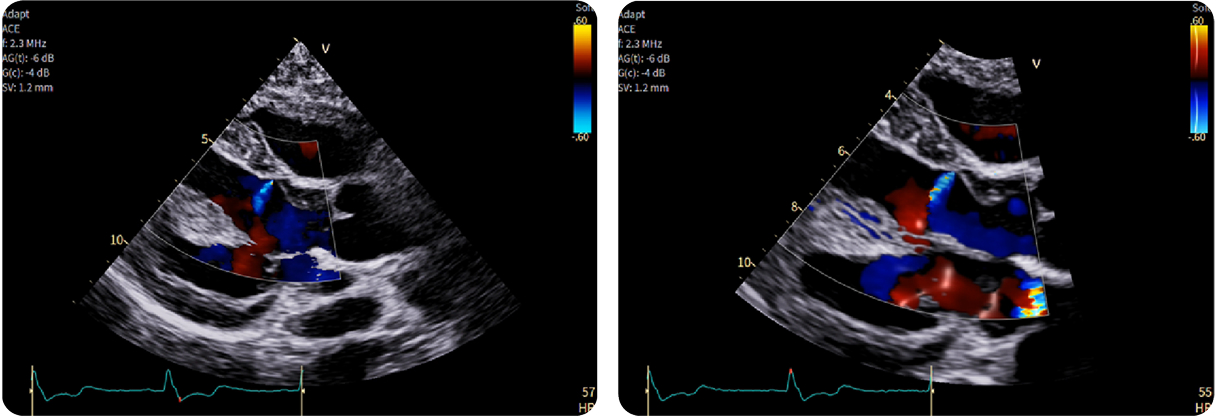

1-Beat Cardiac migliora la qualità diagnostica dell’angio-TC coronarica

L’angio-TC coronarica (CCTA) è uno strumento diagnostico essenziale per l’identificazione delle malattie coronariche, ma la sua affidabilità può essere compromessa nei pazienti con frequenza cardiaca elevata. Grazie ai progressi tecnologici, la modalità 1-Beat Cardiac consente ora di ottenere immagini di alta qualità anche in condizioni di elevata frequenza cardiaca.